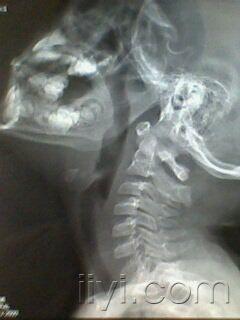

正常腺样体片子

pas标准:≧10mm:属正常范围6~10mm:视腺样体生理性或中度肥大≤5mm

儿童腺样体肥大影像表现及诊断标准

深度解析丨儿童腺样体肥大影像表现及诊断标准